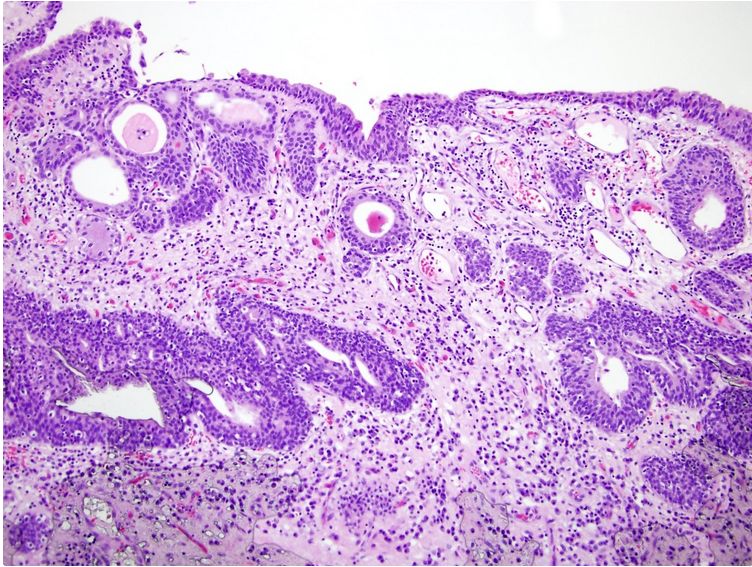

Incidental finding in bladder bx?

Dx?

Histo features?

Cause?

Dx: nephrogenic adenoma

Cause: metaplastic change of the urothelium in response to chronic infection, calculi, or prolonged catheterization. Sometimes implants.

Histo: : heterogeneous with numerous architectural patterns that are often admixed including small tubular, papillary, sheet-like with clear cytoplasm (diffuse), fibromyxoid, and flat. The lesional cells are low cuboidal and may have a hobnail arrangement in tubules or on papillae; thick BM material often surrounds the tubules. Small tubules often have an intraluminal blue myxoid material that may simulate a signet ring cell.